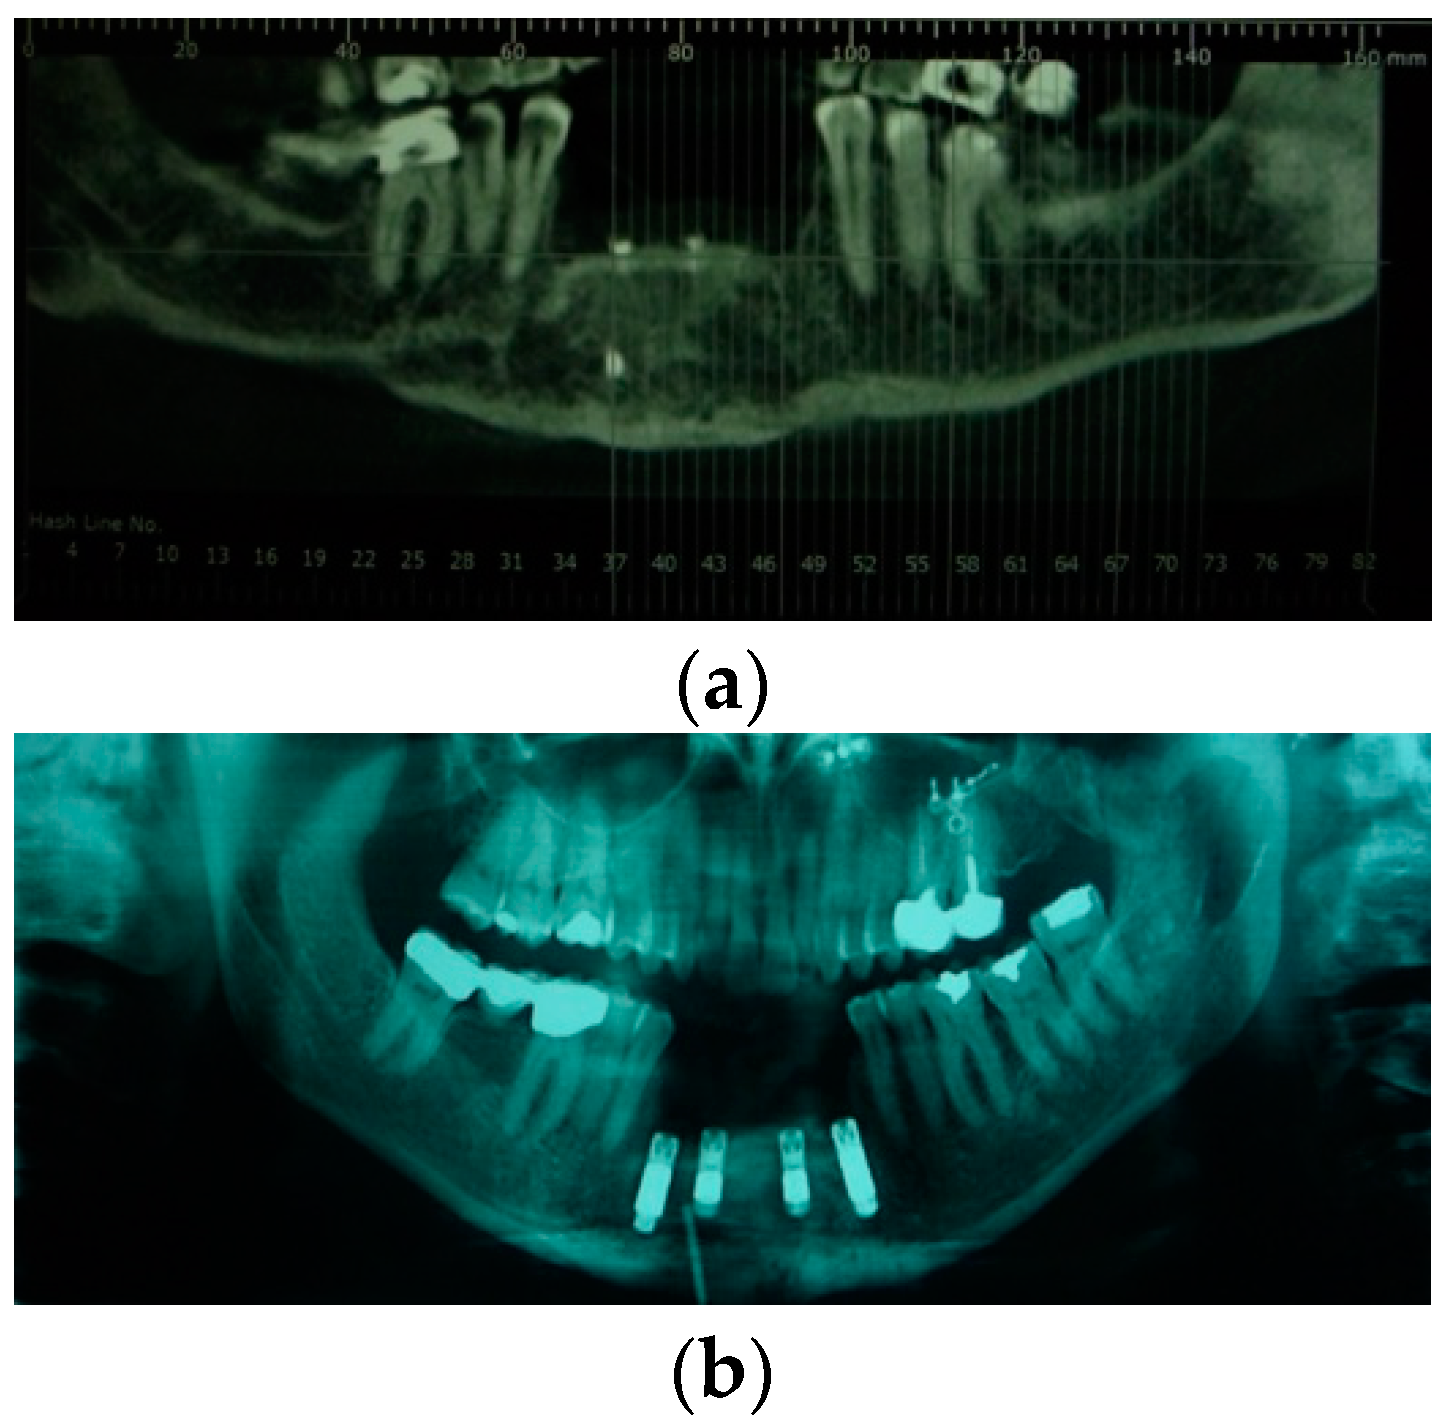

| 2 | 33/M | Low-velocity injury | T4, Lower maxilla, Alveolar bone, Gingival and Soft tissue | Alveolar Resection III quad. | No | Fixed implant-supported prosthesis (n. 7 dental implants) |

| 9 | 21/M | Low-velocity injury | T3, Lower maxilla, Alveolar bone, Gingival and Soft tissue | Anterior Alveolar Resection | No | Fixed implant-supported prosthesis (n. 4 dental implants) |